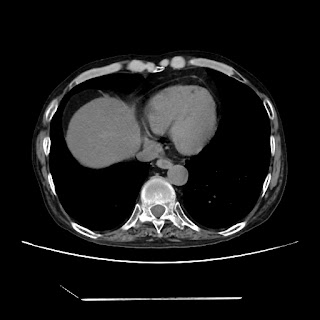

HRCT done on 17Mar16